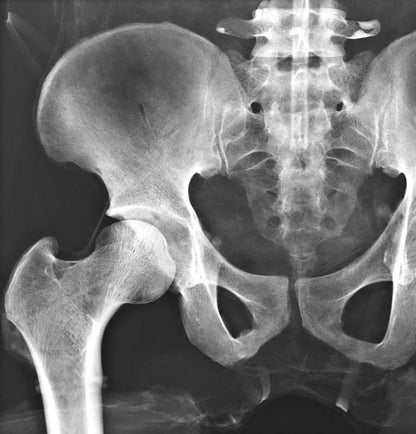

The whole-body X-ray phantom serves for practical training in projection radiography as well as in positioning and positioning techniques. It enables the production of realistic X-ray images under training conditions and depicts anatomical structures in their natural size.

The phantom contains a natural human skeleton. Additionally, the outlines of the larynx, lungs, heart, and kidneys are integrated, appearing as shadows on the X-ray images. This allows for the creation of images that accurately reflect the conditions found in patients. The use of a real skeleton enables the identification of bony landmarks that are not visible in plastic models.

The joints are mounted with full mobility, allowing positioning in common radiological standard positions, including special positions such as the frog position and pronation and supination of the forearm. The arms can be raised, so the phantom can also be used for bone examinations in CT scans. Particular attention was paid during assembly to the realistic representation of the joint spaces.

Each phantom is a handcrafted, unique piece. Variations in size, design, and appearance are possible. Depending on the model, pathological findings may be present. The revised design was developed in collaboration with a German training institution for medical-technical radiology assistants and meets the requirements of modern training concepts.